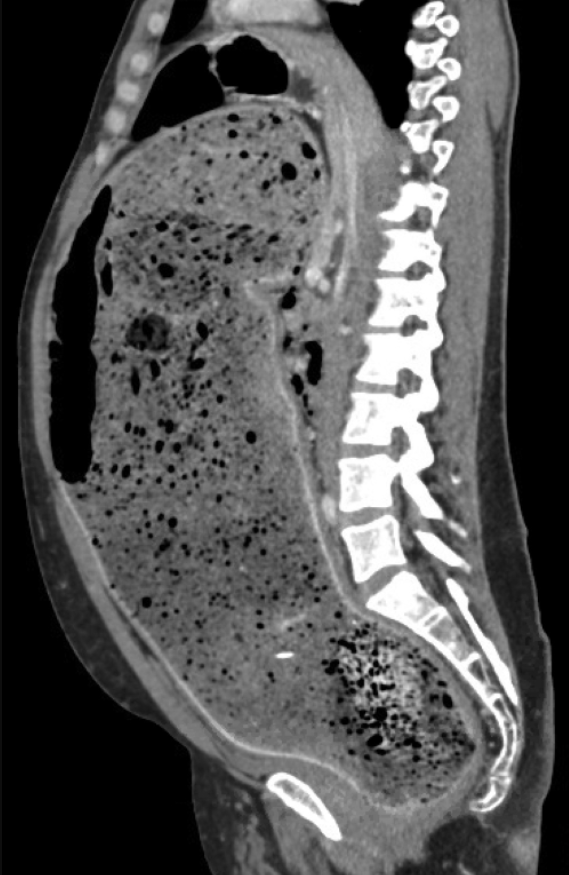

Before NG cleanout and disimpaction:

After NG cleanout and disimpaction/Neostigmine: